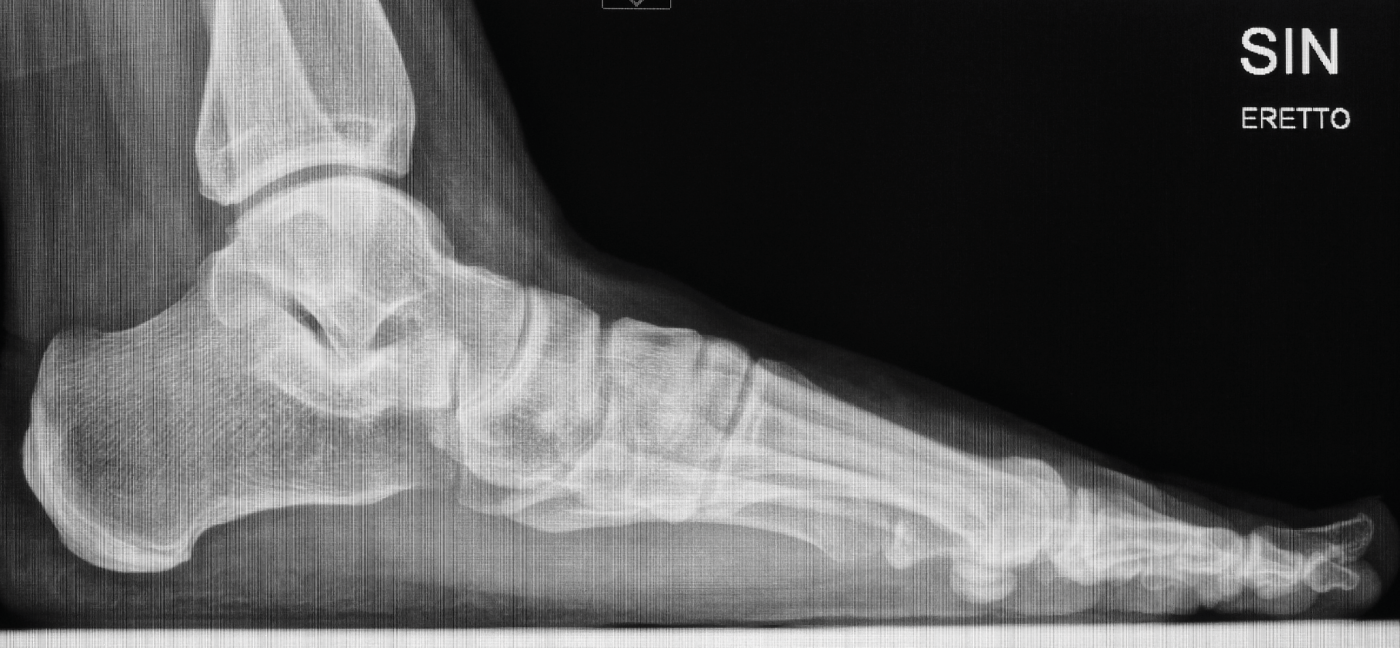

Röntgenbilder

Für die OP-Planung sind auch detaillierte Röntgenbilder unerlässlich. Sie dokumentieren die Fußknochen und den Grad der Fehlstellung aus verschiedenen Blickwinkeln. Am linken Fuß ist die Abweichung des Längsgewölbes und die Verschiebung der Knochen deutlich erkennbar.

Röntgenkontrolle

Die Kontrollaufnahmen unmittelbar nach dem Eingriff zeigen die anatomisch korrigierte Fußform. Die eingebrachten Schrauben stützen den Aufbau so lange bis der Knochen vollständig verheilt ist.